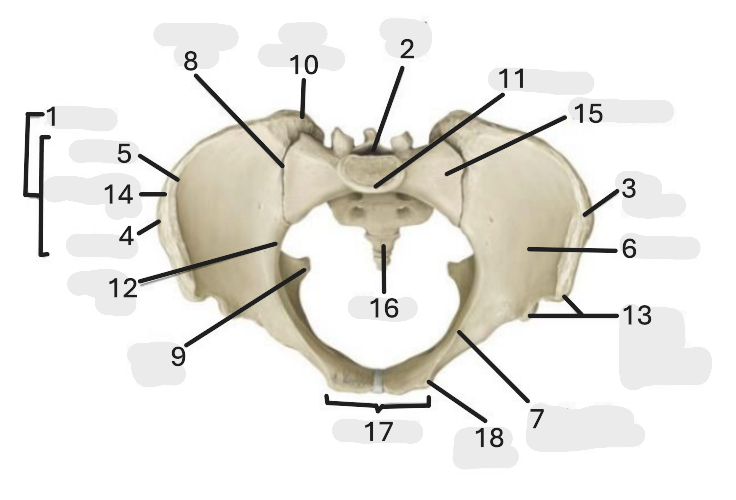

Where is the pelvic inlet

1

Where is the sacro-iliac joint

2

Where is the pubic tubercle

3

Where are the S1 body

4

Where is the ischial spine

5

Where is the ala of sacrum

6

Where is the anterior superior iliac spine

7

Where is the ischiopubic ramus

8

Where is the coccyx

9

Where is the obturator foramen

10

Where is the pubic symphysis

11

Where is the ischial tuberosity

12